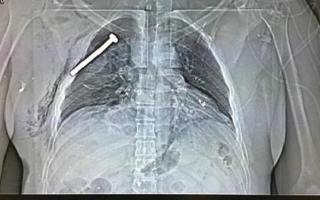

صور بأشعة (إكس) لمسامير اخترقت ضحايا تفجيرات بروكسل

من صور وزعتها الوكالات عن قتلى وجرحى تفجيرات بروكسل، واحدة لمصاب بلجيكي، كشفت أن منفذيها استخدموا عبوات محشوة بمسامير، بنية قتل أكبر عدد من الأشخاص، فحين وجدوه يئن وينزف من صدره وهو ملقى في أرض قاعة المطار، نقلوه إلى مستشفى عسكري بضاحية Neder-over-Heembeek وهي في شمال بروكسل، وفيه عالجوه بقسم الطوارئ وصوروا صدره بأشعة إكس، ووجدوا مسماراً نافذاً فيه حتى رئته، وسريعاً علموا أنه كان ضحية عبوة مسمارية الطراز.

المسمار انتزعوه من صدر المصاب، على حد ما ذكرت صحيفة La Libre Belgique وحتى غيرها من وسائل إعلام بلجيكية، مع شرح قليل ذكرته عن الصورة التي وجدت طريقها أيضاً إلى وسائل إعلام عالمية، ذكرت بدورها أن قتلى وجرحى آخرين لا بد أن مسامير اخترقت أجسامهم، إضافة إلى مسامير أخرى لم تجد ما تخترقه وقد تكون في القاعة التي استهدفها التفجير الإرهابي بمطار بروكسل الدولي.